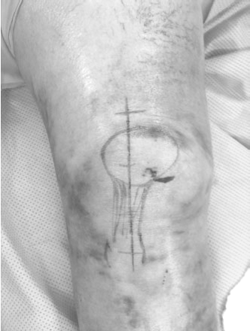

ORIF Patellar fracture

-적응증 : Patellar fracture 슬개골 골절

2.midline incision with respect to the underlying structures of the extensor mechanism

4.Vertically oridented patella fracture reduction